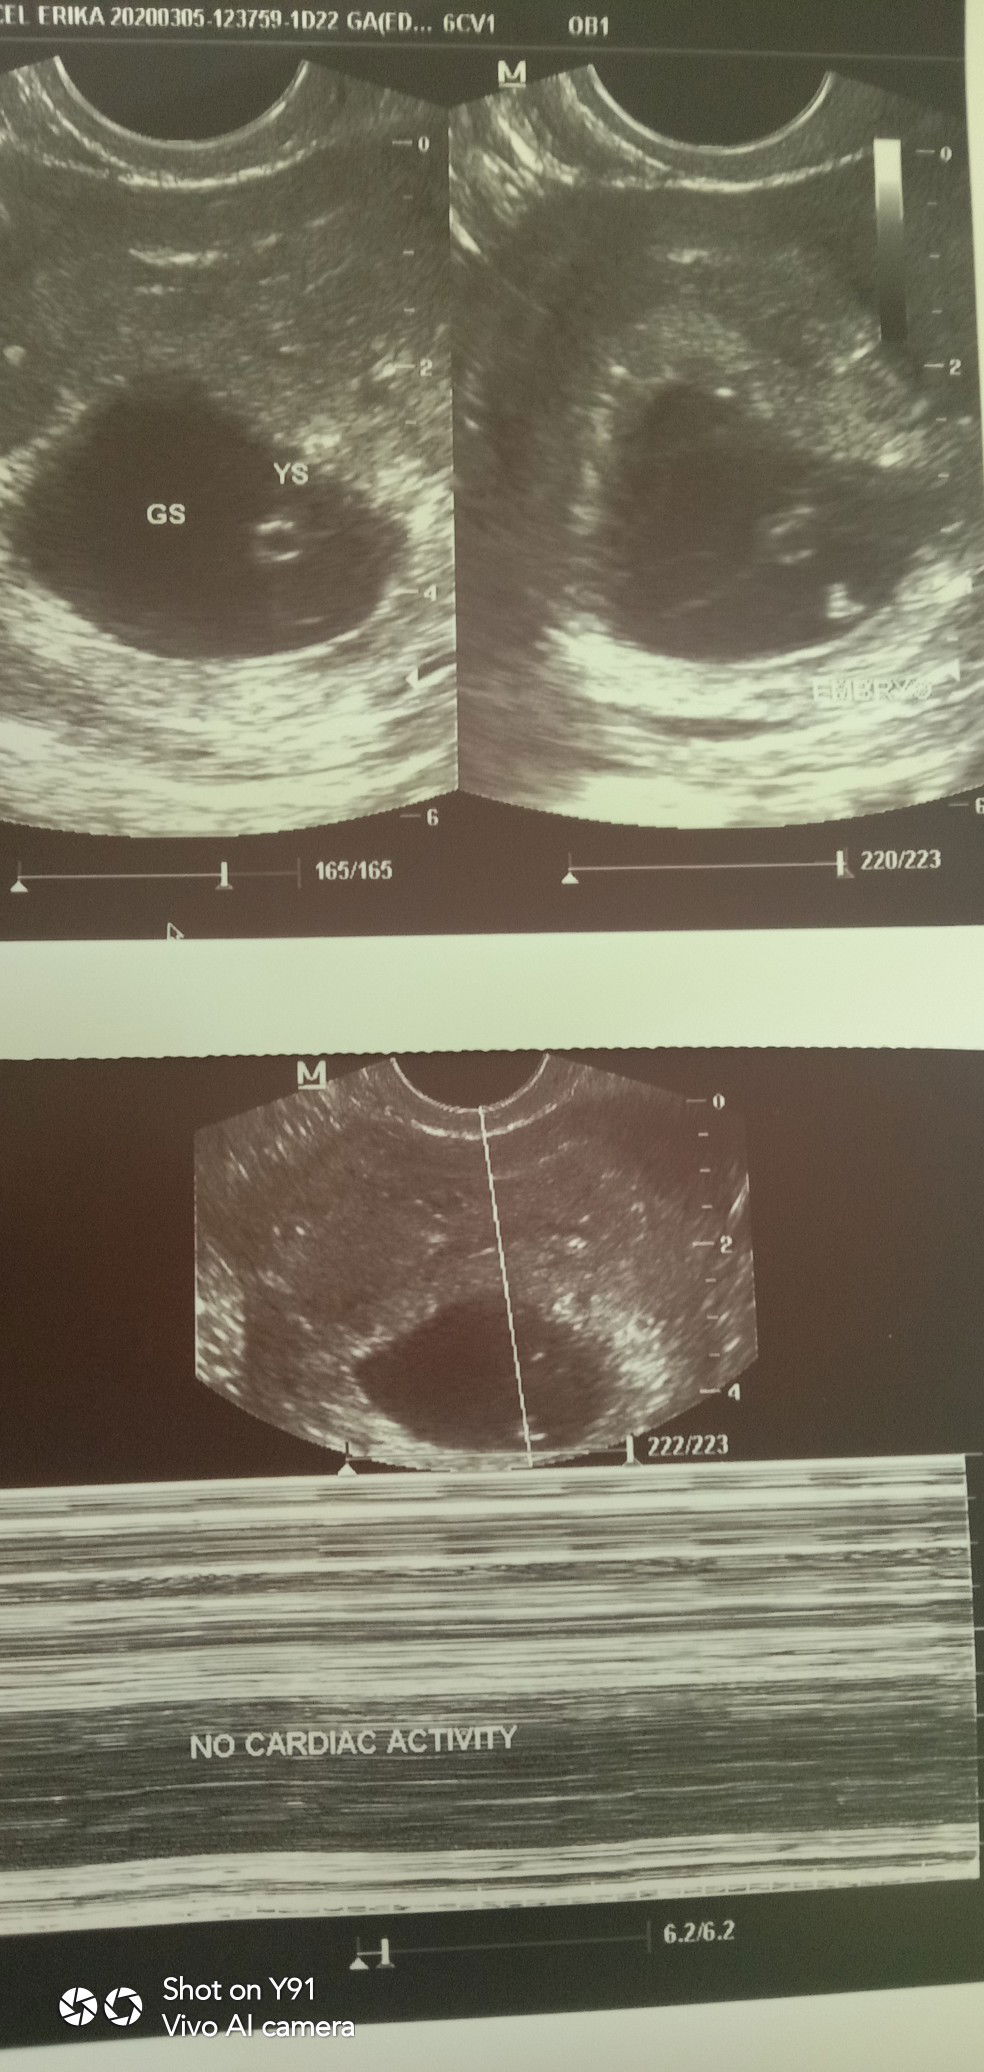

i need your advice ?

Last week (feb 27) sa transV ko my baby is 5 weeks 6days and now (march 5) 6weeks 1 day, sabi ni doc di nag develop si baby and wala din natrace na heart beat. May nakaexperience na din po ba sainyo ng ganito? Iyak ako ng iyak paguwi ko galing sa clinic, antagal namin hinintay na magkababy tapos parang sa salita ni doc wala na yung baby ko ?????

Sana po talaga miscalculated lang po. Im so worried 😭😭